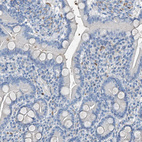

Immunohistochemical staining of human placenta shows moderate cytoplasmic positivity in trophoblastic cells.